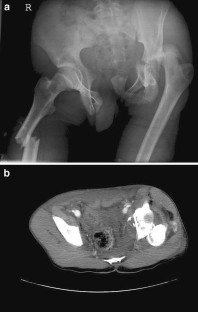

Fig. 1